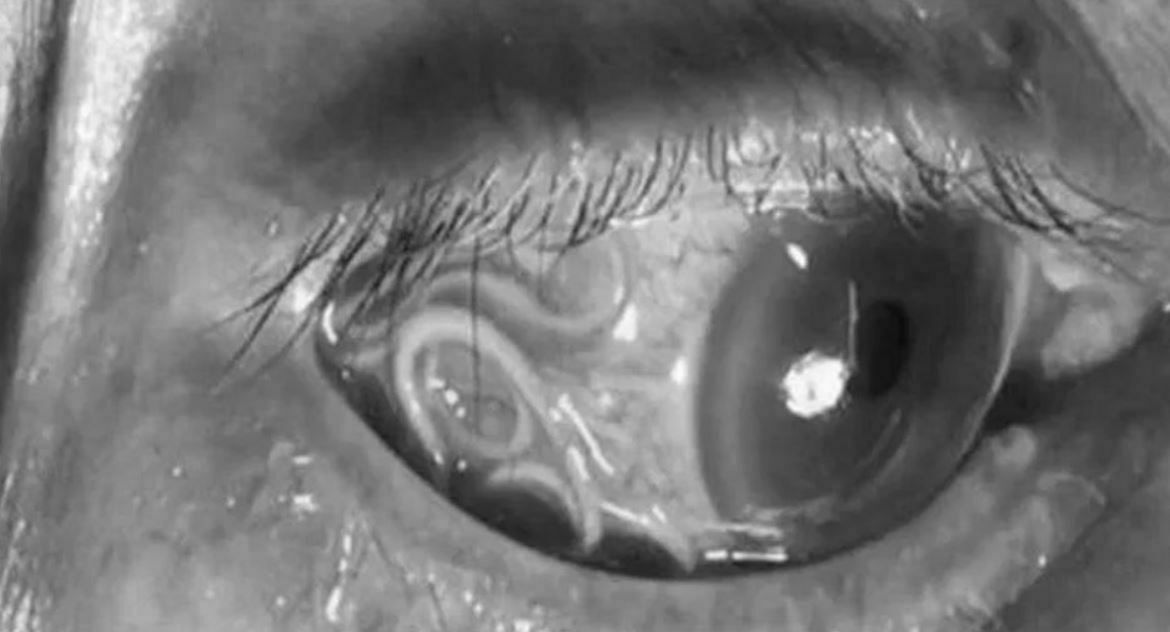

उनको आँखाबाट १५ इन्चको जीवित जुका निकालिएको हो। एक रिपोर्टका अनुसार आँखामा चिलाउन र दुख्न थालेपछि महिलाले सफा पानीले धुने देखि लिएर विभिन्न उपायहरू अपनाउन थालिन् ।

अत्याधिक रूपमा आँखा दुख्न थालेपछि ती महिला अस्पताल पुगेकी थिइन् । उपचारका क्रममा उनको आँखामा १५ इन्च लामो जुका भेटिएको थियो। अस्पताल पुगेकी ति महिलाको आँखा हेरेर डाक्टरहरू नै डराएका थिए ।

चिकित्सले उनको आँखामा देखिएको १५ इन्चको जुका निकाल्नका लागि शल्यक्रिया शुरु गरे । धेरै समय पहिलेदेखि आँखा चिलाउने समस्याबाट ग्रसित भएकी महिलाले आफ्नो आँखामा भएको सुन्दा आफैँ अचम्मित भएकी थिइन् ।

ति महिलालाई शल्यक्रिया गर्ने चिकित्सकहरूका अनुसार आँखाबाट जुका निकाल्न अझै केही समय ढिला गरेमा उनको आँखाको ज्योति गुम्ने सम्भावना अधिक थियो ।

आँखाभित्र नै जुकाको मृत्यु भएको भए आँखामा अन्य समस्या उत्पन्न हुन सक्ने भएकाले आँखाबाट जुका निकाल्नुभन्दा पनि जिउँदो जुका निकाल्नु चिकित्सकहरूका लागि ठूलो चुनौती बनेको थियो । शल्यक्रियापछि बिरामी अहिले स्वस्थ छिन् ।